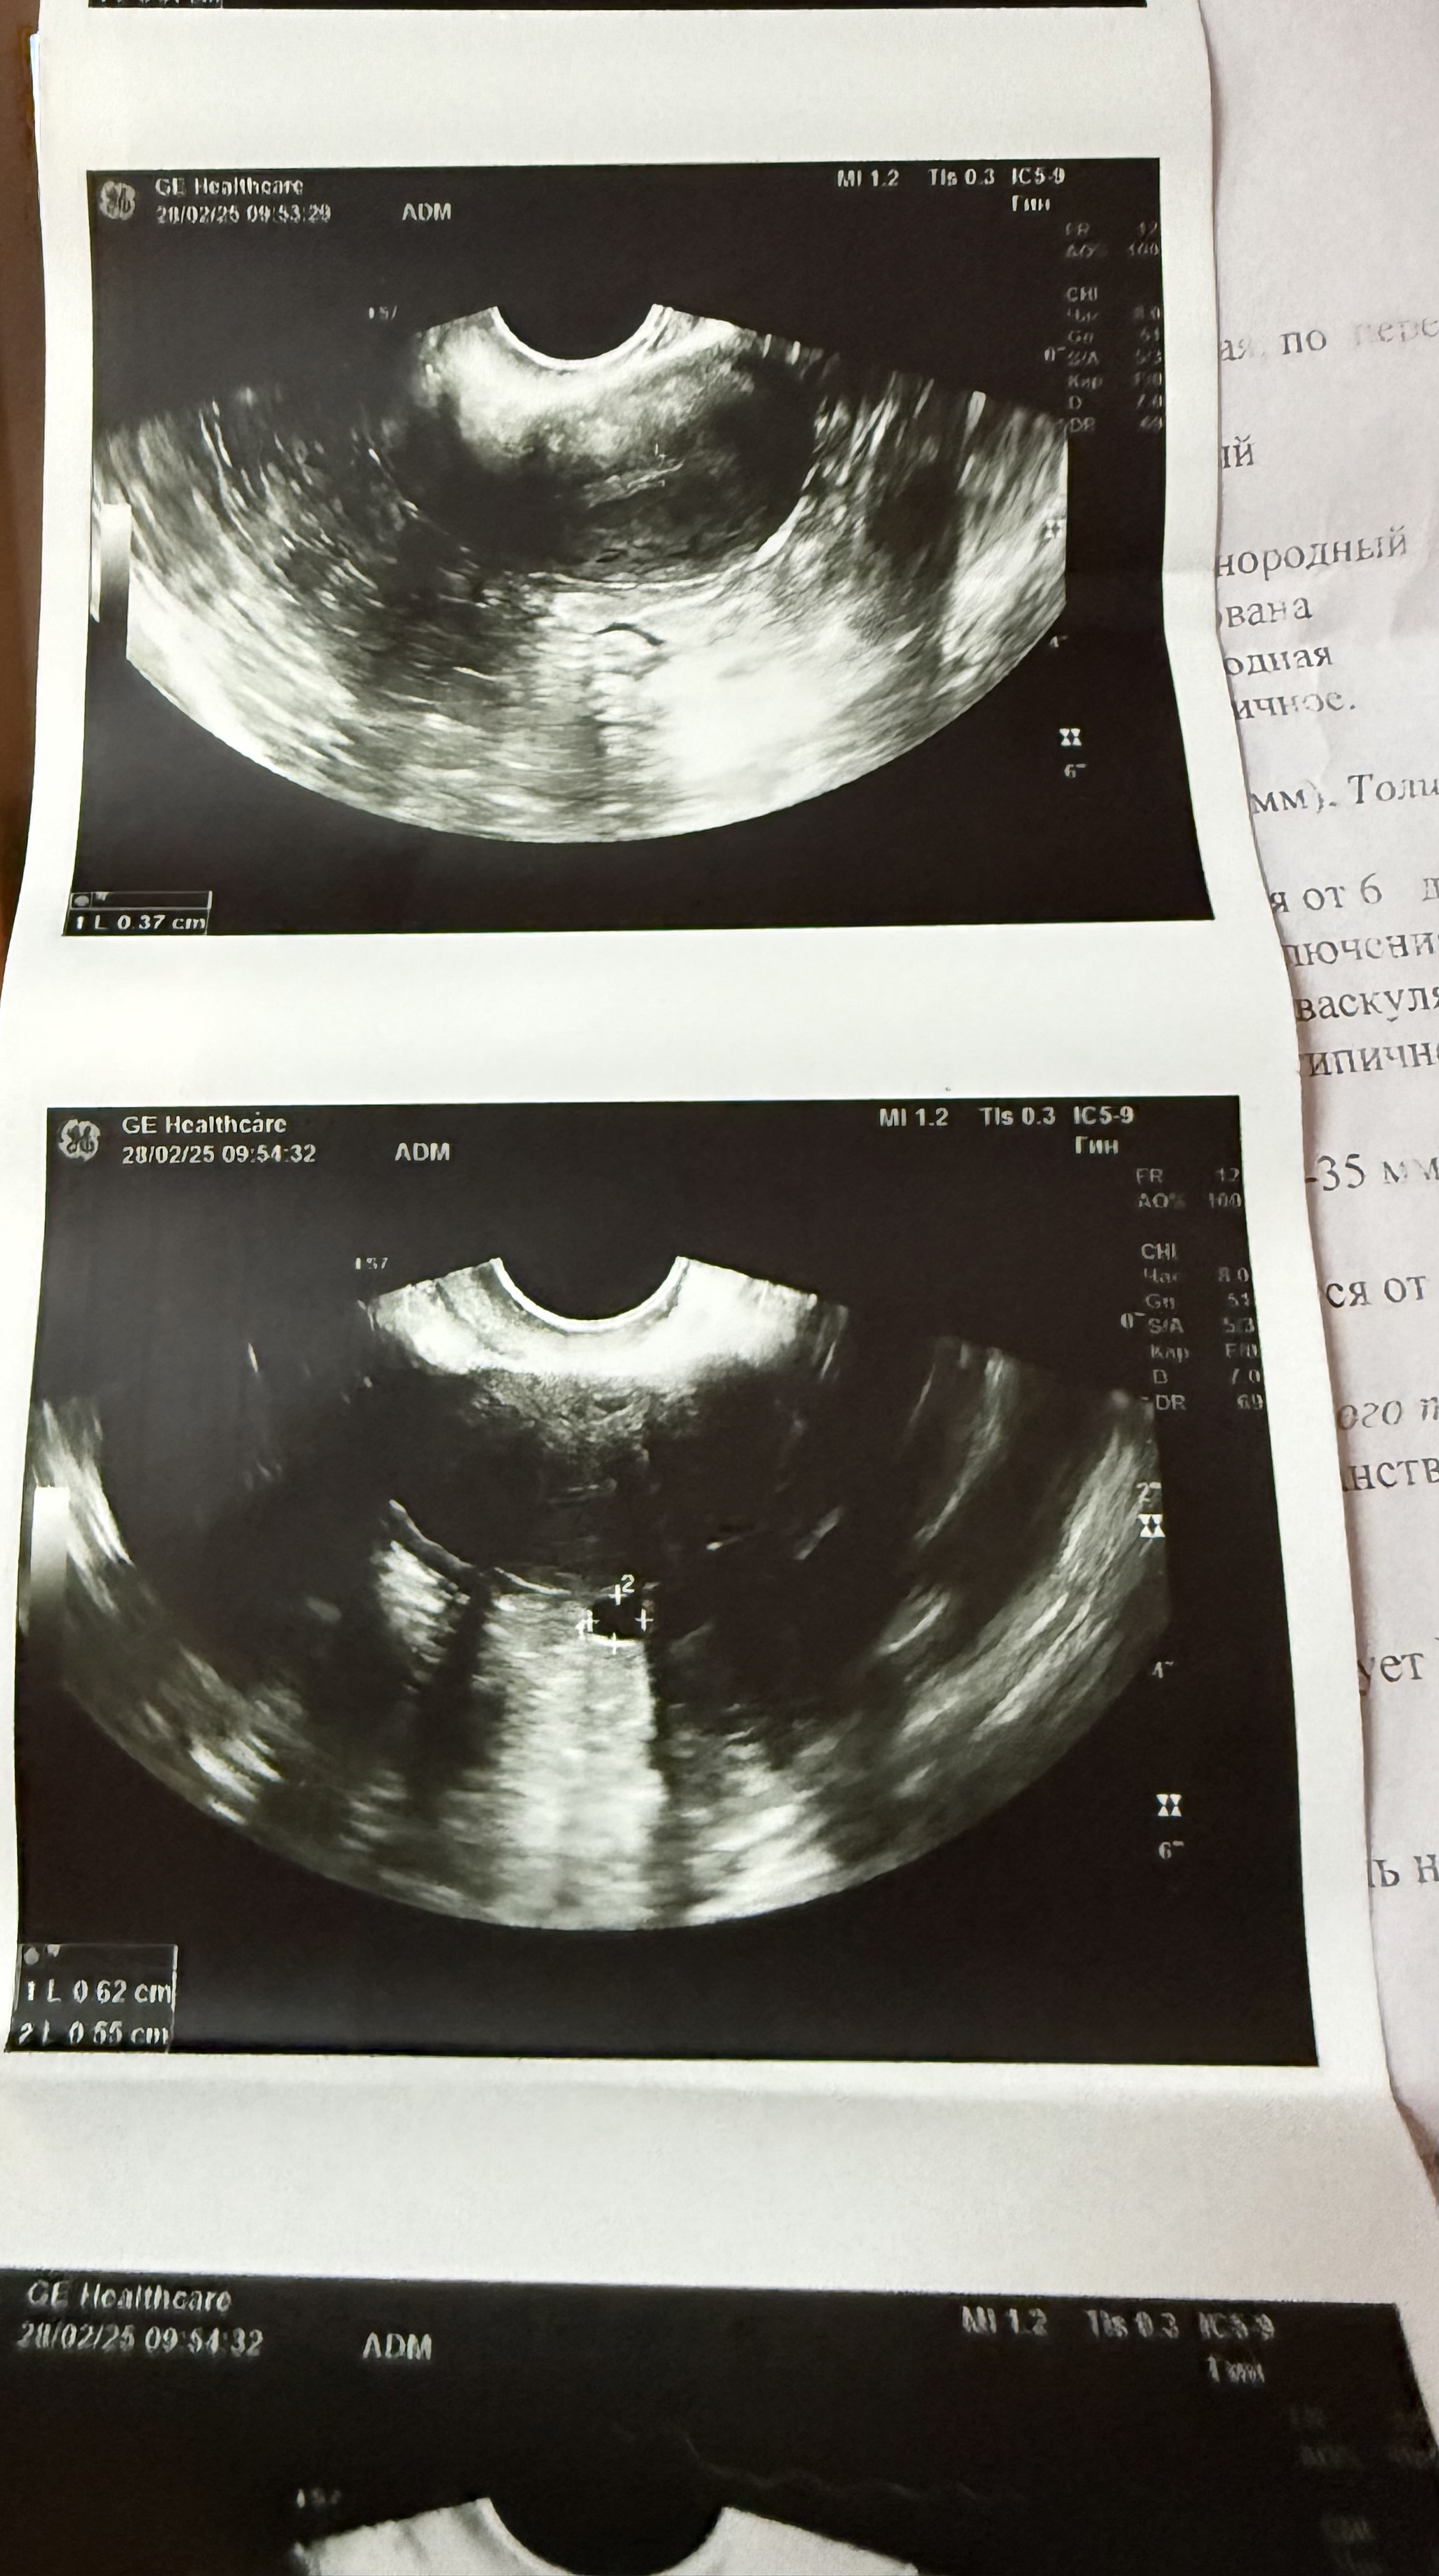

Изображение Изображение Изображение

Ольга Забелина, картина и вправду странная... Экспертное узи и хгч в динамике, все что можно посоветовать. Скорее сорвалась б.

Ольга Забелина, 3 дня назад на узи не было этого шарика

По УЗИ у вас первая фаза менструального цикла, а это значит, что овуляции нет и жёлтого тела то же нет. Гидросальпинкс это гнойное воспаление в маточных трубах обычно. + миома. Вам бы к гинекологу и в стационар и чем быстрее тем лучше.